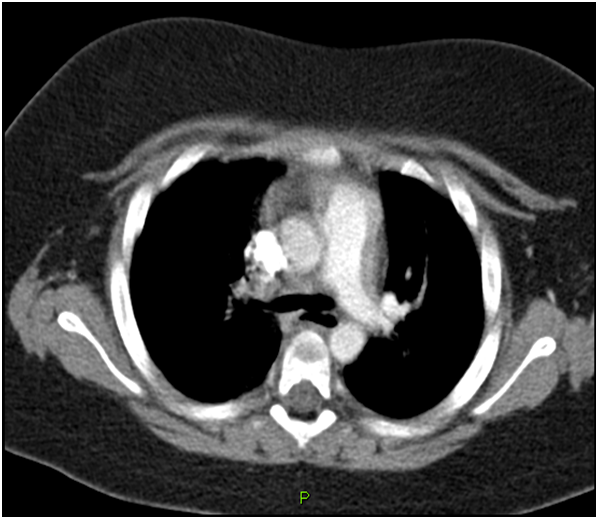

D-dimer was sevenfold the upper limit. A second chest radiograph showed a mild left pleural effusion. Because P.E. was suspected the patient underwent a contrast enhanced computed tomography (CT) of the thorax that demonstrated clots into the upper and lower lobar right pulmonary arteries (Figure 1). The girl was treated with LMWH followed by warfarin with resolution of symptoms. Further laboratory tests for thrombophilia screening revealed methylene tetrahydrofolate reductase heterozygotes mutation with normal homocysteine plasma level and heterozygotes mutation of the Factor II (G20210A). The patient was discharged from hospital on oral anticoagulant therapy for six months and with a hypo-caloric diet.

Figure 1 CT scan of the lungs demonstrating clots in right pulmonary artery.